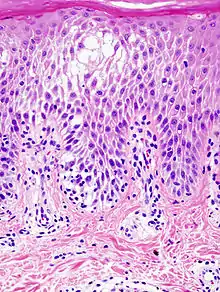

La espongiosis se observa cuando se estudian muestras de una biopsia de piel a través del microscopio, En la capa de Malpigio, las células están más separadas de lo normal y pueden formarse pequeñas vesículas por acumulación de líquido, observándose además la presencia de células inflamatorias como linfocitos.